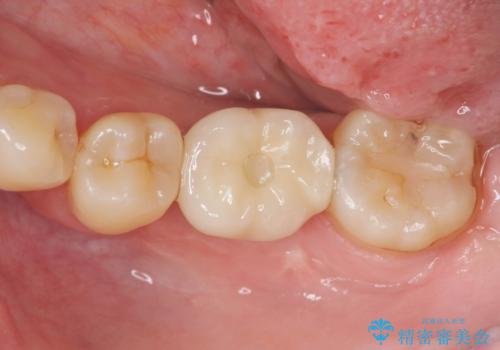

- 44万円(インプラント・アバットメント・ジルコニアクラウン・仮歯)費用は治療当時の料金となります

ブリッジのように前後の歯を削ることなくしっかりと咬合機能の回復を行うことができました。